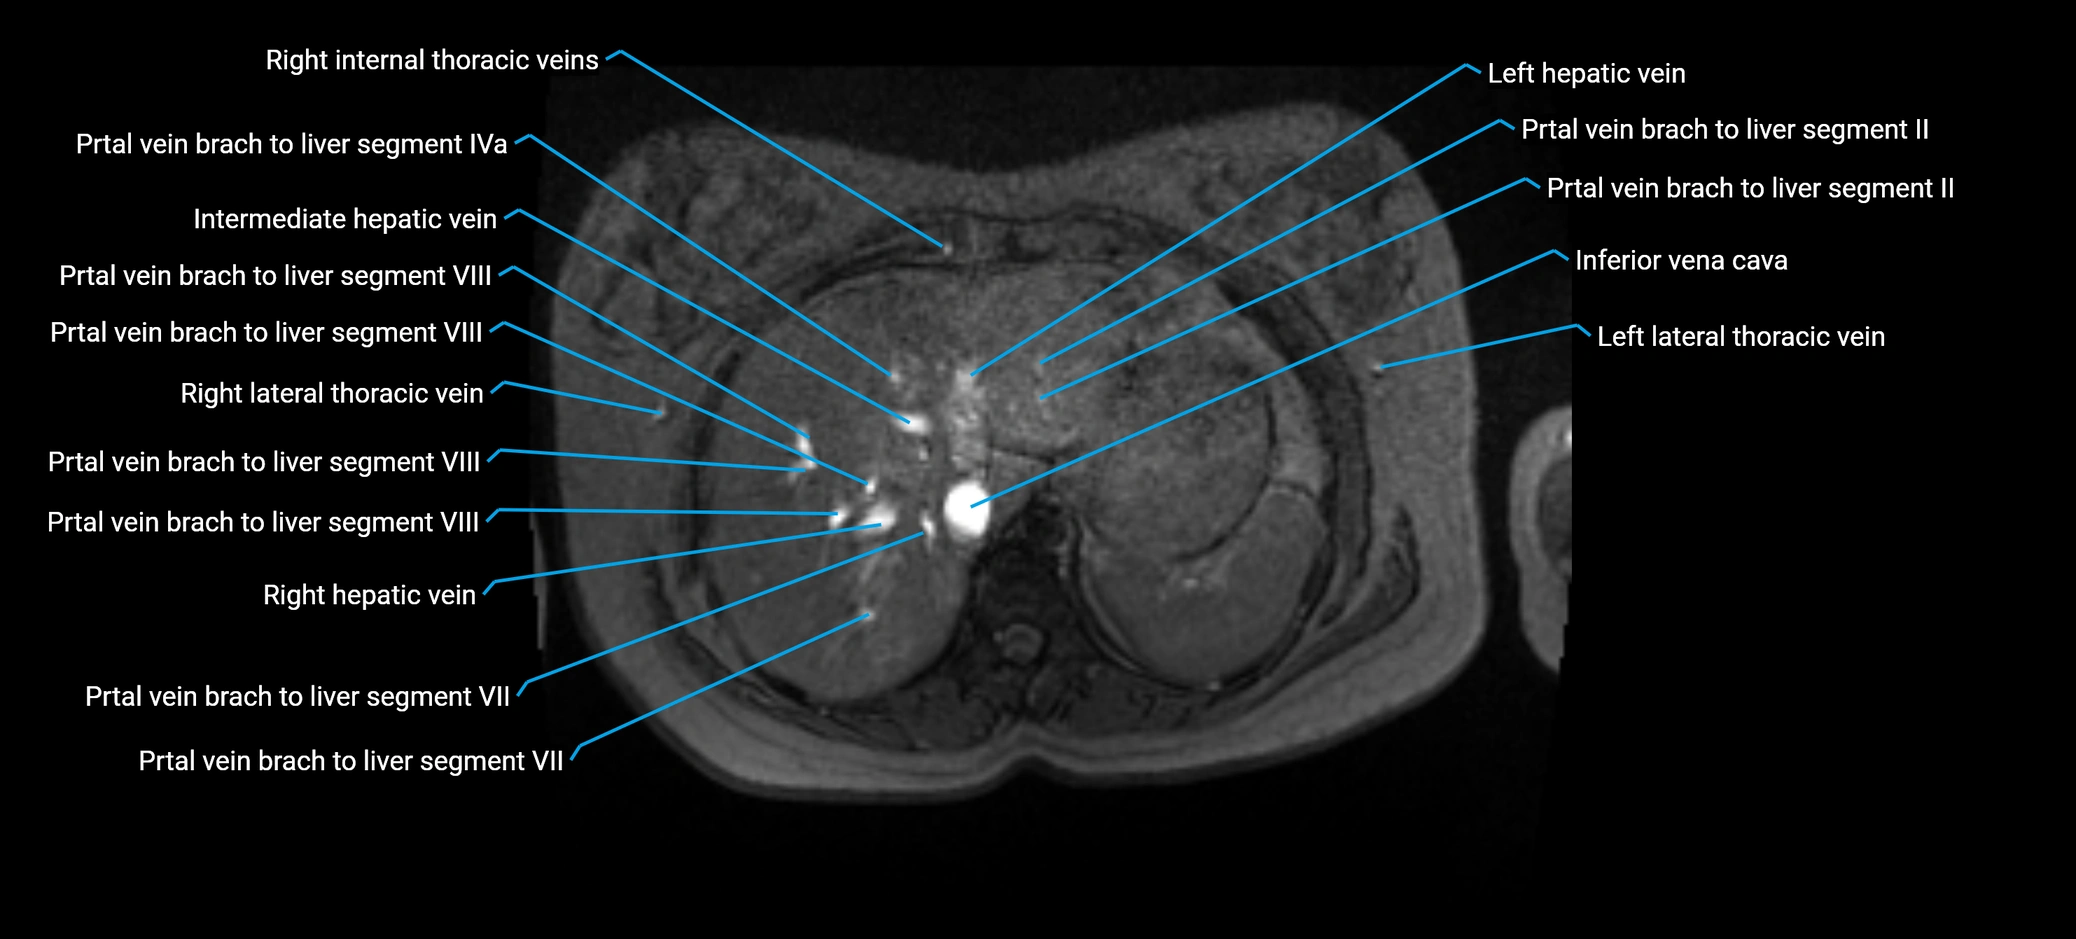

MRV TOF (Time-of-Flight MR Venography):

• Appears as a bright, high-signal vascular channel representing flowing blood

• Clearly shows branching pattern of right portal vein into anterior and posterior branches

• Best in coronal or axial reconstructions for segmental mapping

• No need for contrast, relies on flow-related enhancement

Post-Contrast T1 Fat-Sat GRE:

• Enhances brightly and homogeneously during the portal venous phase

• Clearly delineates branching into segments V and VIII

• Best sequence for evaluating patency, caliber, and anatomic variants

MRI image

image